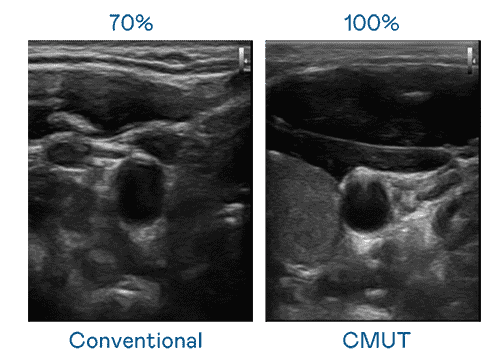

CMUT 技术是一种用电容式微机电元件来产生超音波讯号的技术。。与传统 PZT 压电式技术相比,,CMUT 频宽增加 30%,,更宽频的超音波讯号让影像解析度大幅提升,,,是实现高影像品质医疗超音波扫描、、促进精准医疗发展的关键技术。。。。

大频宽带来超清晰影像

超音波影像的解析度高低,,首先取决于探头能发出的讯号频宽。。彩运网 CMUT 可提供高清晰的超音波讯号,,,提供高频宽、、、、高灵敏度、、影像纹理细节更高的超音波影像,,,,协助医护人员缩短影像判读时间及利用精准的医疗影像进行诊断。。